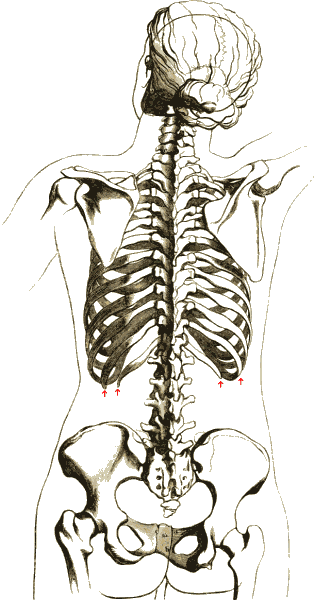

'''가슴우리'''(rib cage영어)는 동물 흉부에 있는 뼈 구조를 말한다. 이 뼈대는 척추와 갈비뼈, 그리고 복장뼈(흉골, sternum영어)로 이루어져 있으며, 몸 안의 중요한 장기인 심장과 폐 등을 감싸 보호하는 역할을 한다.

가슴우리는 구부러진 모양의 갈비뼈들이 복장뼈 및 척추와 연결되어 새장(cage)과 같은 형태를 이룬다. 이러한 구조 덕분에 외부 충격으로부터 내부 장기를 효과적으로 보호할 수 있다.

2. 1. 척추와의 연결

인간의 척주를 구성하는 33개의 척추뼈 중에서, 가슴우리는 가슴 부위의 척추인 흉추 TH1부터 TH12까지 총 12개의 뼈와 연결되어 있다.[1][2] 모든 갈비뼈는 뒤쪽에서 이 흉추에 하나씩 붙어 있으며, 붙는 순서에 따라 위에서부터 1번부터 12번까지 번호가 매겨진다.갈비뼈는 앞쪽에서 복장뼈(흉골)와 어떻게 연결되는지에 따라 크게 두 종류로 나눌 수 있다.

갈비뼈 사이의 공간을 늑간 공간이라고 부른다. 이 공간에는 늑간근과 신경혈관다발(늑간 신경, 늑간 동맥, 늑간 정맥 포함)이 위치한다.[4] 가슴우리의 표면은 흉요근막으로 덮여 있으며, 이는 목 근육, 등 근육, 가슴 근육, 복부 근육 등이 부착되는 지점을 제공한다.